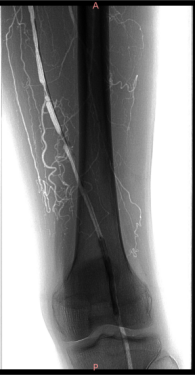

★ 造影评估

右侧股动脉翻山入路,经鞘管造影显示下肢动脉多发硬化改变。

左侧股浅动脉中下段局部重度钙化狭窄闭塞,左股浅动脉下段,腘动脉局部中度钙化狭窄。

股浅动脉

腘动脉

★ 术后造影

病变解除,管腔及血流恢复通畅,未见夹层及造影剂外渗